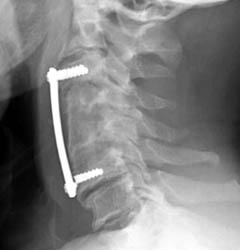

Lateral radiograph taken three weeks post-operatively shows the anterior

fusion C3-C6 with no hardware complications. The strut graft appears intact and

well seated and the spine is in normal anatomic alignment |

Lateral radiograph now 10 weeks post-operatively demonstrates interval

fracturing of the two cortical screws in the vertebral body of C6. Superior

displacement of the screws relative to the distal plate. Furthermore, the bone

graft has tilted dorsally in its superior aspect as well.